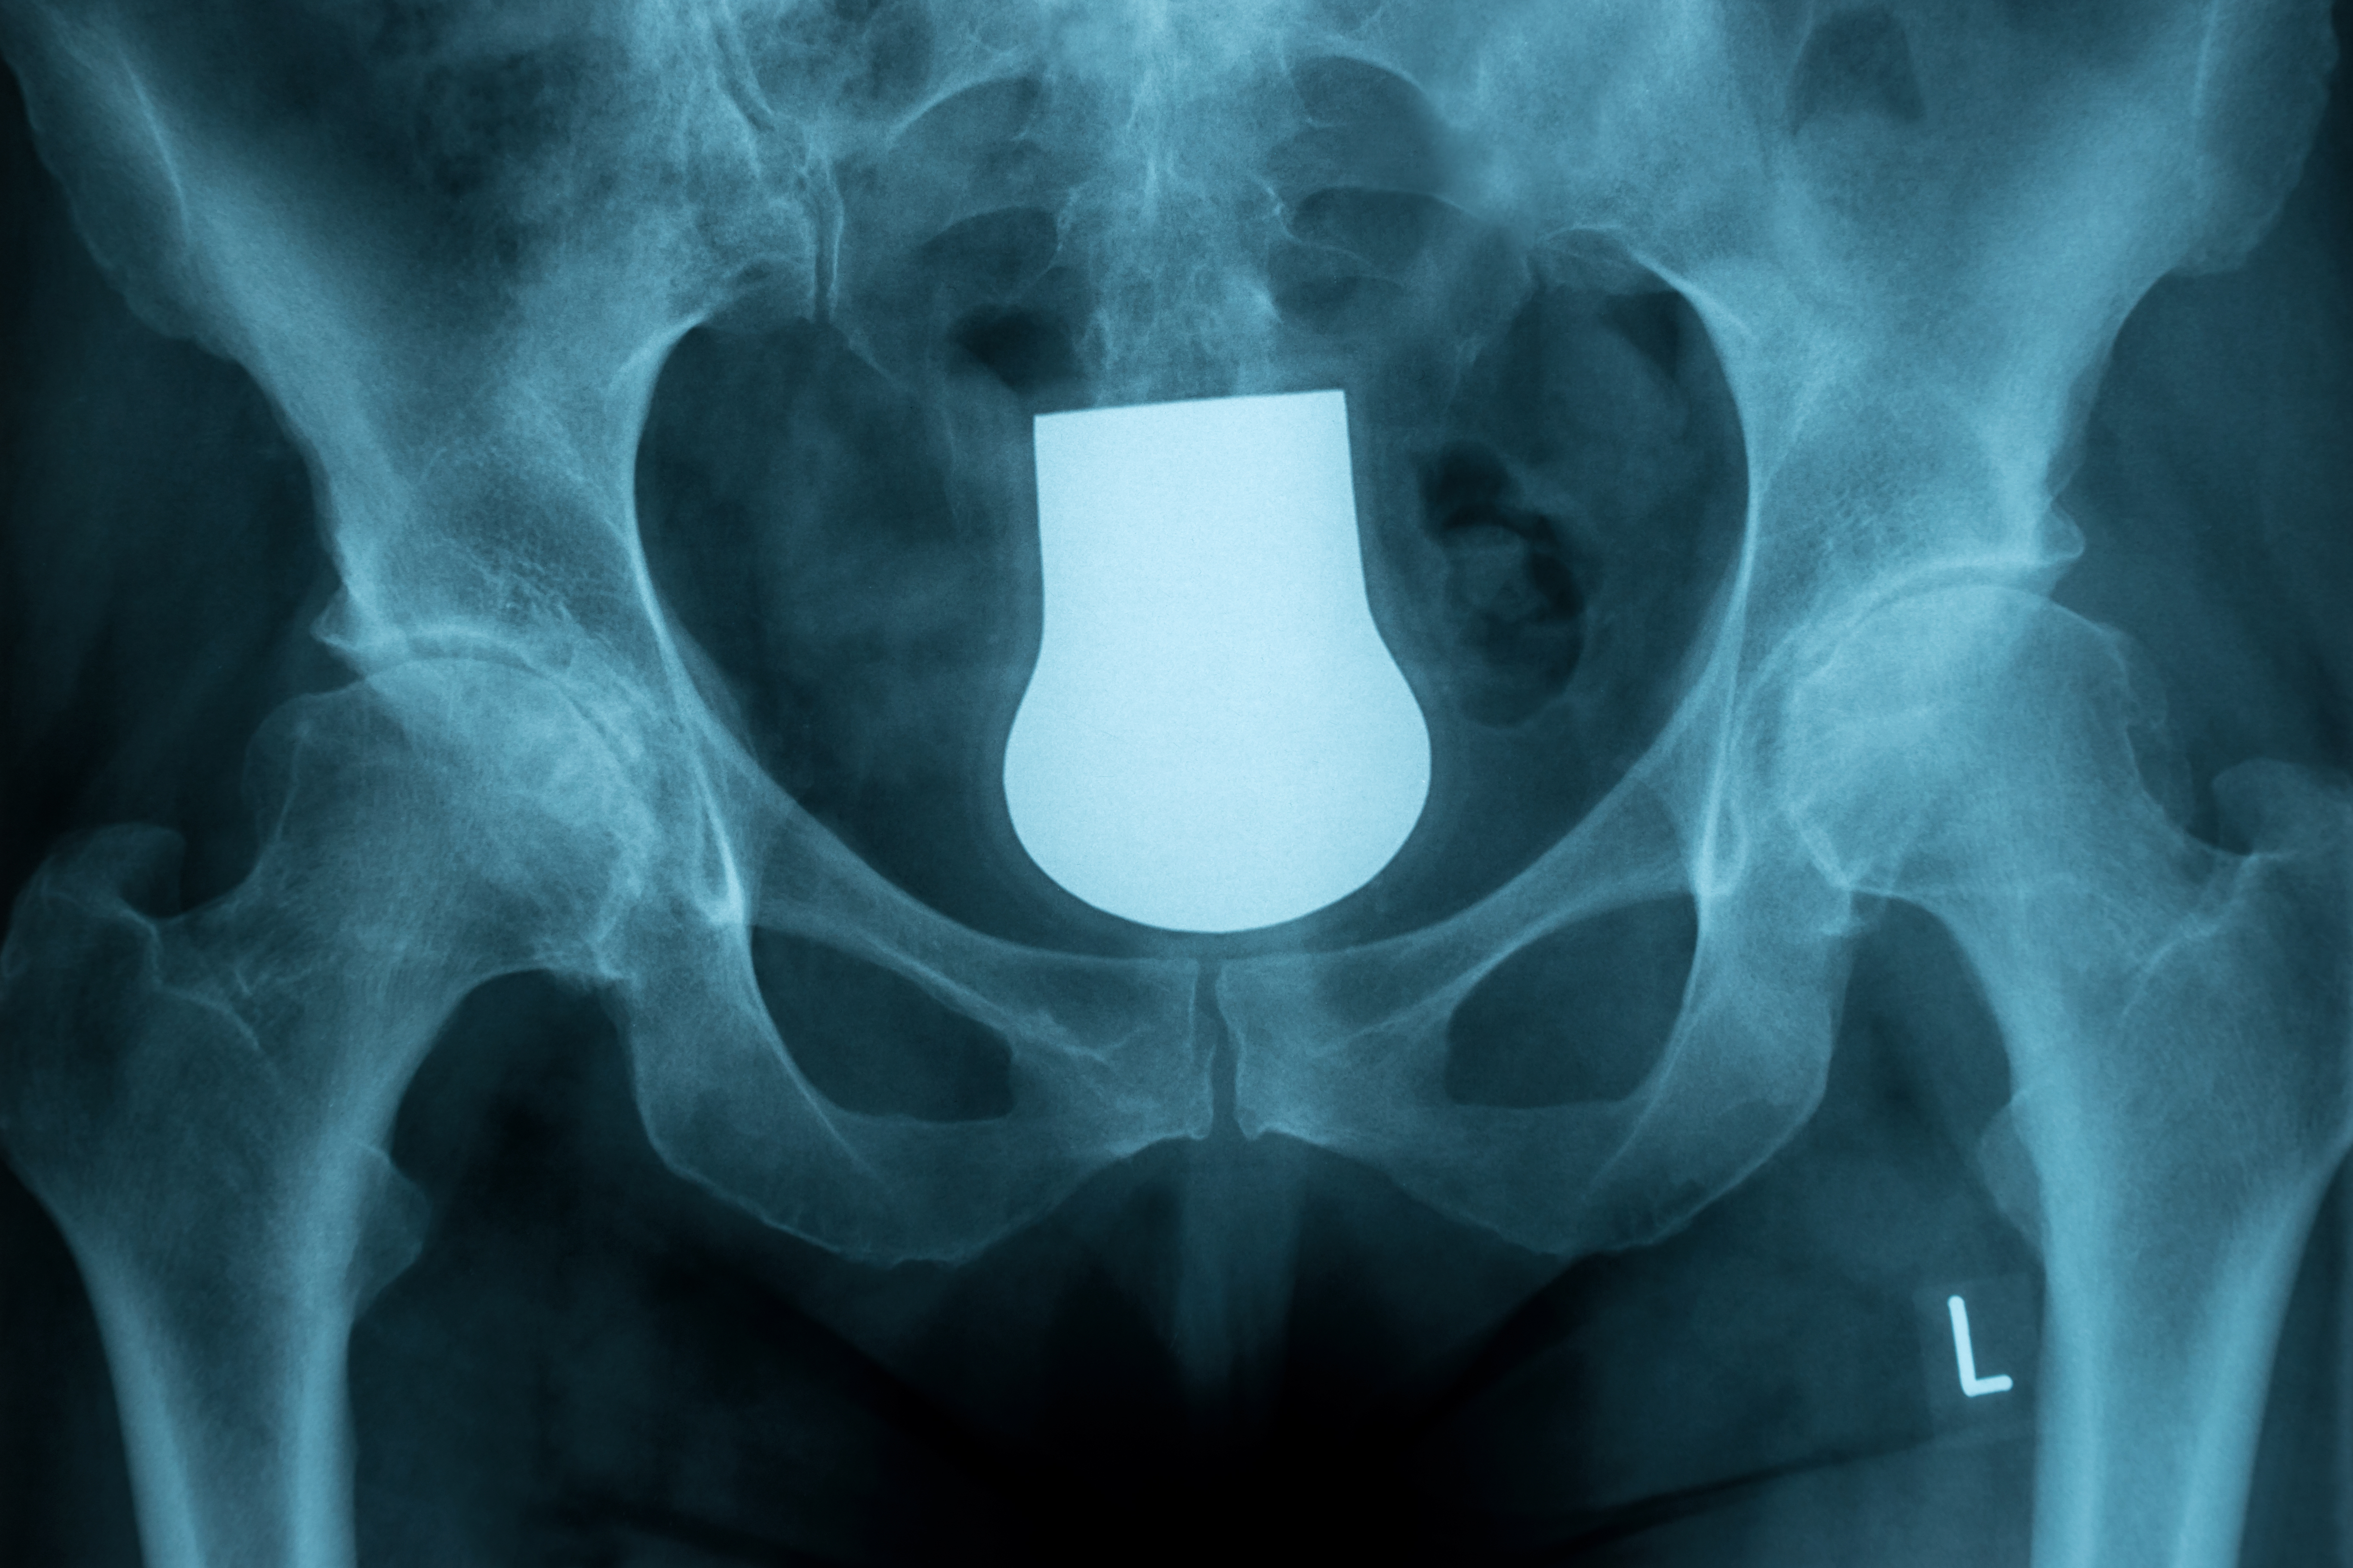

髋关节的X线解剖及应用技巧,最全总结!

目前,一张标准的X片图像仍然能为我们的临床诊断与决策提供重要的依据。为了全面评估髋部疼痛患者的病情,X线片图像仍然是有效手段。